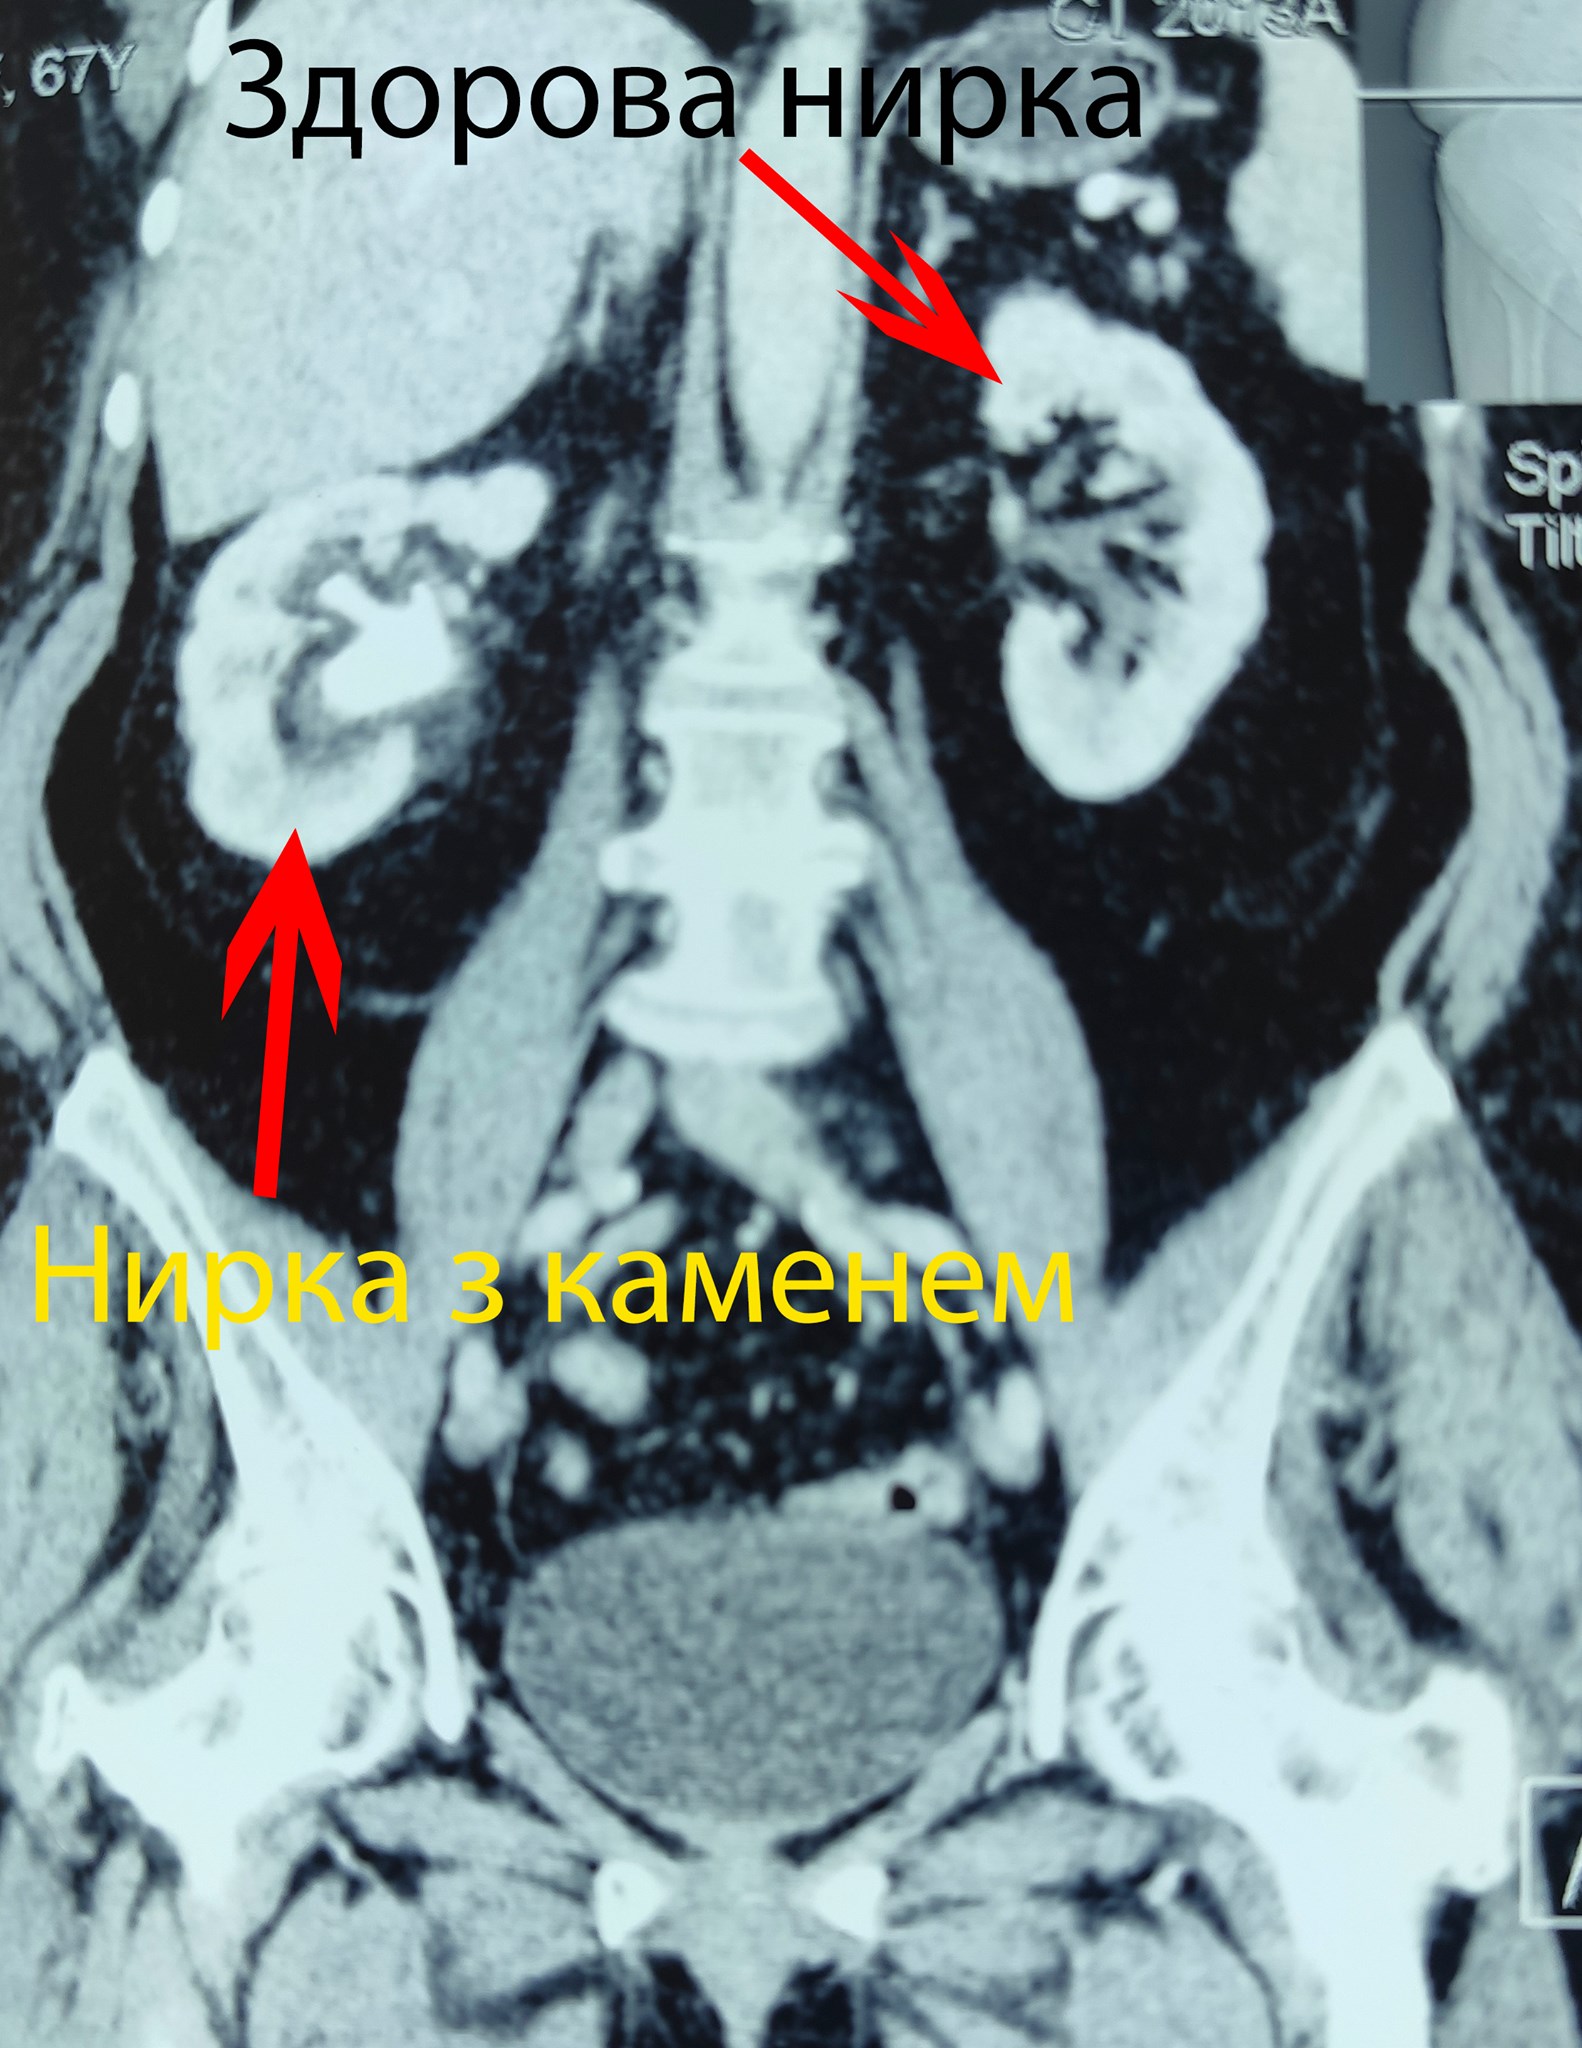

Як повідомив ліккар, камінь займав всю порожнину нирки. Під час операції конкремент поступово вдалося видалити повністю. Видалили кораловидний камінь правої нирки через єдиний мініатюрний прокол на шкірі 5 мм.